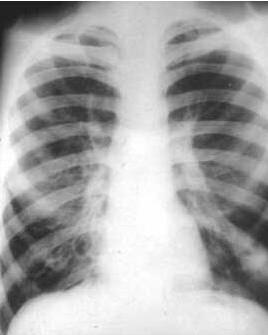

支气管扩张系支气管因反复感染及分泌物阻塞或先天性发育缺陷等因素,造成管壁破坏、变形和扩张的一种慢性化脓性疾病。病变一般为不可逆性,进展较慢。约50%的成人患者,症状常起自小儿时期。主要表现为经常发热、咳嗽、多痰、甚至咯血。近年由于加强呼吸道感染疾病的防治,以及抗生素的及时应用,发病率已有所减少,症状也较过去为轻。[1]